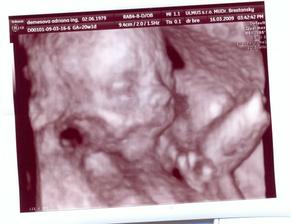

15.01.2009 nás čaká ďalšie sono:D, už teraz sa teškáme....08.01.2009 špinenie, panika...tak šups doktorovi - predpísal nám Utrogestan, MagneB6 a Ascorutin. Máme si dávať denne dva citróny a dve lyžičky medíku. Dostali sme štipľavú injekciu, ale bábätku našťastie veselo bije srdiečko...a máme pre istotu aj fotečky:D